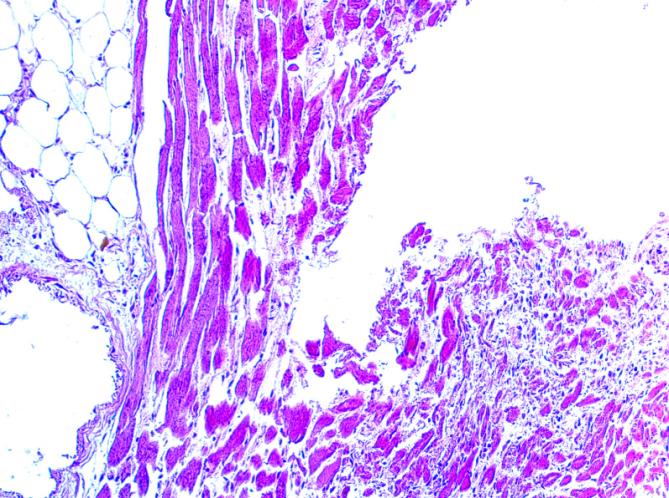

3.病理组织学检查:脑组织毛细血管广泛淤血,未见出血及坏死灶;右冠状动脉狭窄(图9),左心室前壁心肌细胞呈嗜伊红色增强,心肌细胞排列紊乱,心肌纤维增长增粗,部分区域可见大面积新鲜坏死区,心肌轮廓尚存,细胞核消失,核缩、核溶,胞浆呈均质细颗粒状,间质有大量中性粒细胞浸润,坏死心肌组织间有新鲜凝血块,部分区域可见心肌组织被大量的纤维组织代替(图11、图12);肺泡壁毛细血管扩张淤血,肺泡壁增厚,肺泡腔内充满大量粉红色液体并有少量红细胞,部分区域可见到心衰细胞(图10);肝细胞排列整齐,毛细血管扩张淤血,无假小叶形成,汇管区未见异常细胞;脾窦扩张,淤血,脾小体中央动脉无异常改变;胰自溶,结构模糊,胰间质及周围脂肪组织未见灶性坏死;双侧肾脏皮髓质分界清晰,肾小球毛细血管正常,近远曲小管细胞肿胀,间隙增宽,呈淤血改变。

(图9)右冠状动脉狭窄(图10)肺水肿及“心衰细胞”

(图11)心左前壁细胞呈嗜伊红色、心肌细胞坏死(图12)心左前壁细胞呈嗜伊红色、心肌细胞坏死